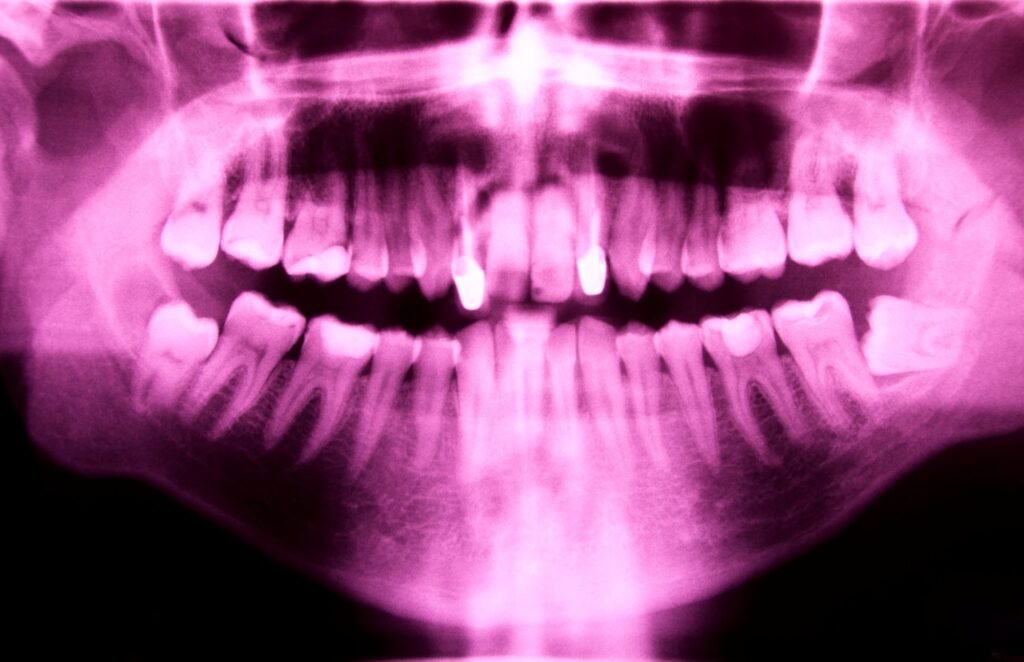

Cuando un paciente nos dice que le han explicado que “no tiene hueso” para un implante, casi siempre hablamos de lo mismo: tras perder una pieza, el hueso se va reabsorbiendo con el tiempo y, en la zona posterior del maxilar superior, además el seno maxilar puede ir ocupando parte de ese espacio. Esa combinación […]